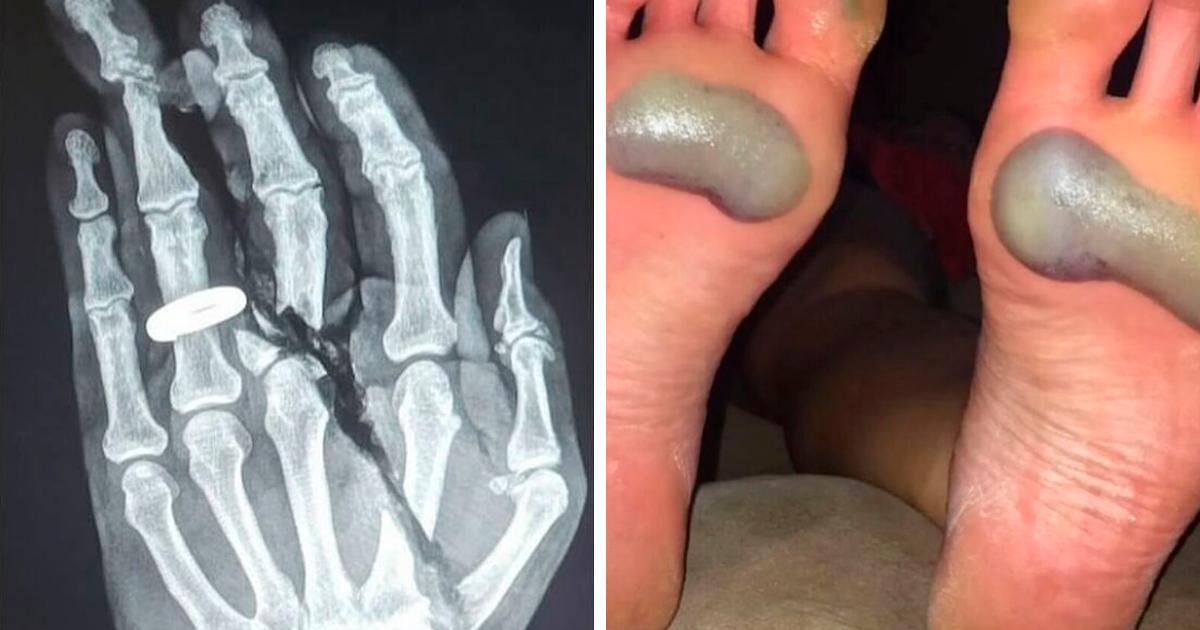

Esta foto muestra las congelaciones de un escalador que casi perdió los dedos de los pies mientras intentaba salvar a un compañero de equipo herido mientras escalaba el Monte Everest